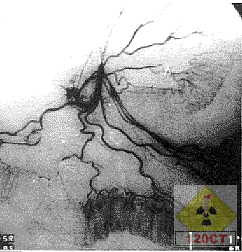

(五)選擇性血管造影近年來已廣泛套用於消化道出血的檢查。1963年在犬實驗中證實:腸道出血速度達0.5ml/min時通過選擇性腸系膜動脈或腹腔動脈造影可以顯示造影劑外溢現象,1989年上海醫科大學華山醫院放射科在22條家犬實驗中,表明來自動脈的出血待其速率達1m時才能見到造影劑的外溢現象;在27例下消化道出血病人,24例選擇性血管造影見有異常發現,其中15例顯示出血部位造影劑外溢,9例顯示異常血管改變,餘3例為假陰性,診斷符合率達88.9%。但選擇性血管造影須通過股動脈插管的操作,屬於損傷性檢查,是其缺點。

無法檢出小腸的出血病變。放射性核素顯像雖對顯示腸道出血的敏感性很高,但其特異性太差,其顯示的出血部位常不確定,故實用價值不大。凡鋇灌腸、雙對比造影以及內窺鏡檢查未能找出下消化道出血的病因時,尤其是急性大量腸道出血以及腸道血管畸形、血管發育不良等病例,選擇性動脈造影有其指征,且在某些病例還可進行介入放射學治療。